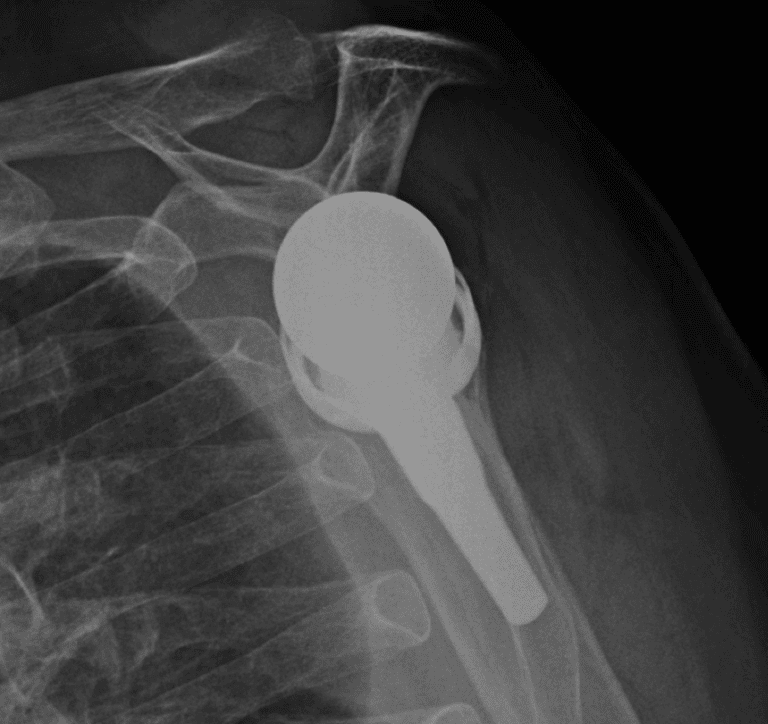

Arthrex, Apex

Selected